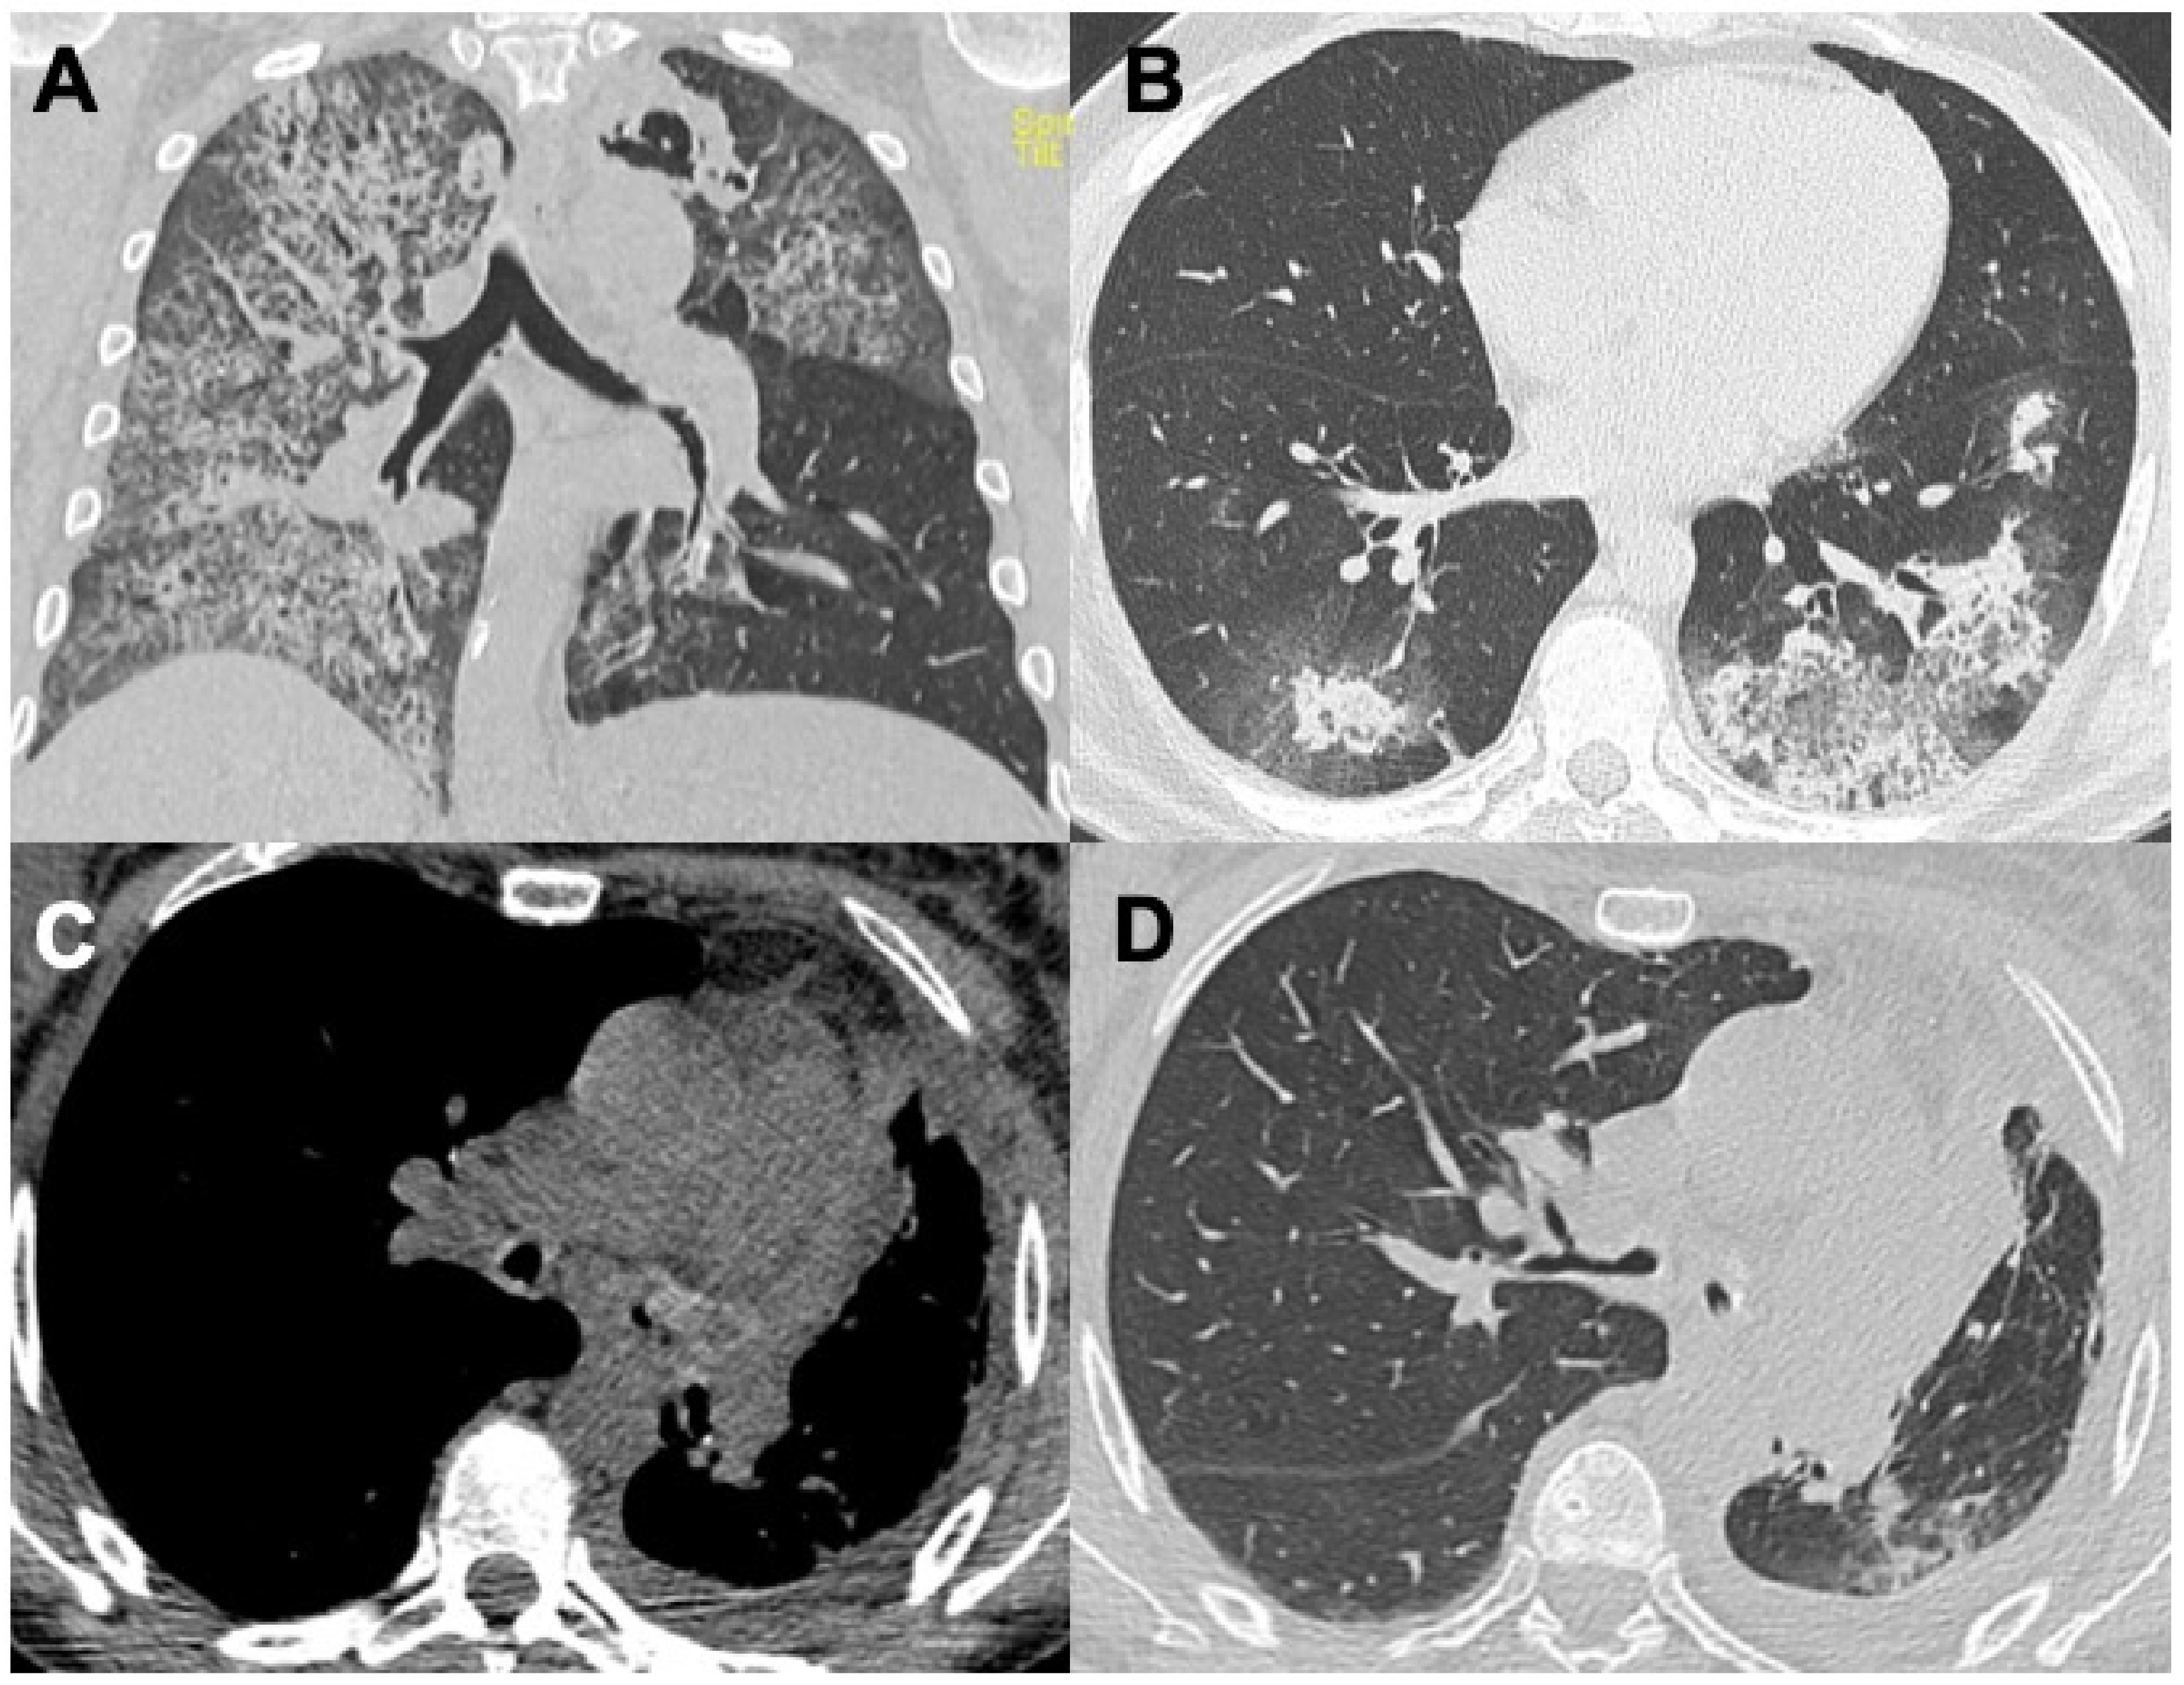

2.3. Granulomatosis with Polyangiitis (GPA)

| GPA | Tracheobronchial involvement (15–55%); bronchiectasis | Nodules (up to 50%); consolidations; GGO (25–50%) and a “crazy-paving” appearance; diffuse alveolar hemorrhage (22–30%) | Pleural effusion (15%); pleuritis; pneumothorax | Pulmonary artery stenosis |